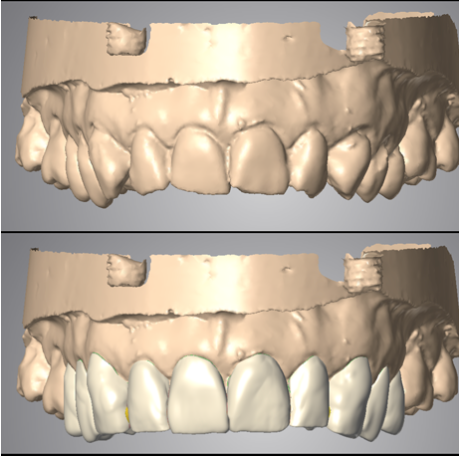

I Fase o studio del caso: con l'ausilio di impronte preliminari, grazie all'ausilio di speciali dispositivi digitali, verrà creata una ceratura diagnostica, ovvero una riproduzione digitale di come dovrà essere il vostro sorriso finito in termini di estetica e funzione, presentazione del caso al paziente, eventuali modifiche ad estetica e funzione saranno possibili in questa fase;

III fase, posizionamento della protesi sugli impianti: fase chirurgica: con il supporto del Laboratorio Odontotecnico Design Dentale (www.designdentale.it) e della Dottoressa Daniela Gasparini, entro poche ore saremo in grado di fissare gli elementi dentali direttamente sugli impianti inseriti durante la prima fase chirurgica. Ogni protesi è personalizzata e il risultato estetico sarà assolutamente naturale: questo è possibile anche grazie allo studio del caso preliminare effettuato pre-intervento con l’ausilio di foto ed impronte di ogni singolo paziente e tecnologia digitale CADCAM.

Studio dettagliato del caso, con tecnologia CAD-CAM

Ci preoccupiamo di rendere ogni lavoro unico, diverso e personalizzato. Perchè ogni sorriso e ogni bocca è differente. Ti verranno prese delle impronte preliminari che verranno inviate al laboratorio; Verranno scattate delle foto per analizzare al meglio la fisionomia del viso; Ti verrà fatto scegliere il colore dei nuovi denti che preferisci e che meglio si sposa con le caratteristiche estetiche della persona.